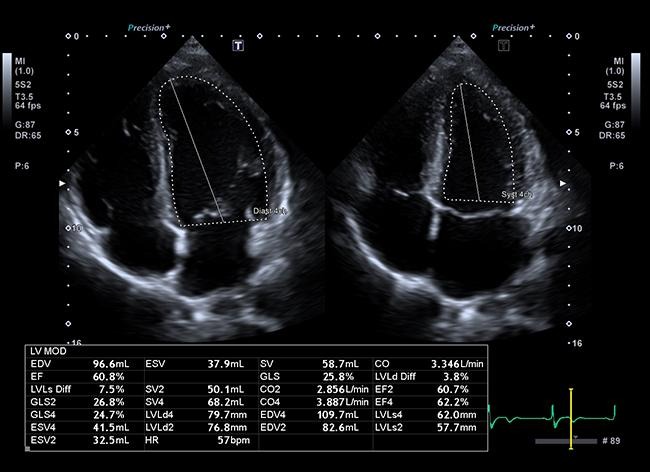

超音波診断装置 (Aplio i600、Aplio αVerifia:キャノンメディカルシステムズ)

Canon Aplio i600

​心臓エコー

​心臓の形、動き、血液の流れをリアルタイムで観察します。

​わかること:心機能(ポンプの力)、弁膜症(弁の逆流や狭窄)、心肥大など。

​こんな方に: 動悸・息切れ・胸の痛みがある方、血圧が高い方、足のむくみが気になる方。